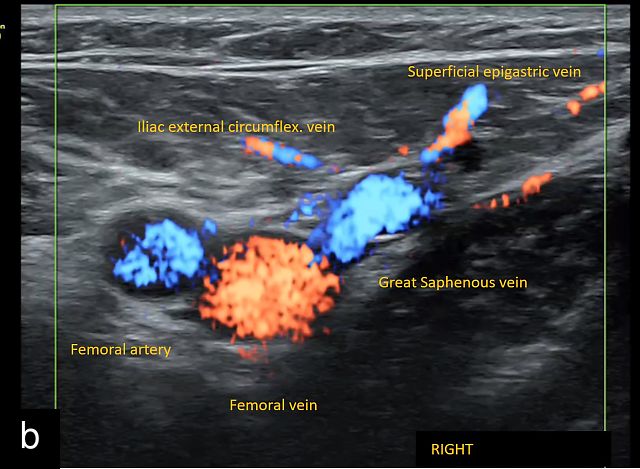

- the saphenofemoral junction, visible in transverse section with the tributary veins of the great saphenous vein (‘snail sign’) (Figure 1b)

![]() | ![]() | ![]() |

Anatomical landmarks for location of the inguinal lymph nodes on ultrasound. (a) Valley or V sign. (b) Snail sign. (c) Hill sign. EIA, external iliac artery; EIV, external iliac vein; FA, femoral artery; FV, femoral vein; PT, pubic tubercle